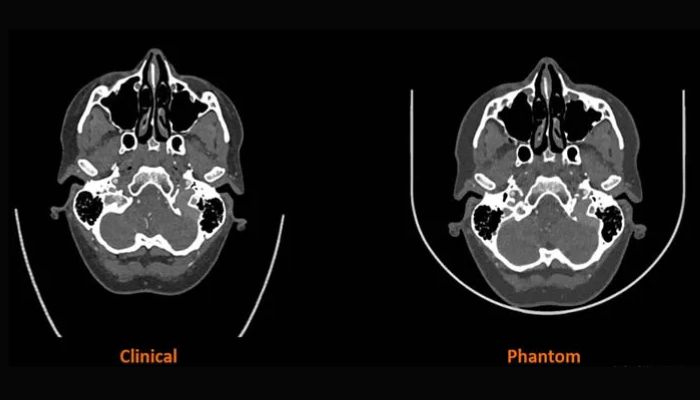

A key advantage of the material is the ability to tune Hounsfield unit values. This tuning allows printed structures to mimic bone, gray matter, fat, veins, or any feature expected in a clinical scan. Early work between Stratasys and Siemens Healthineers shows that RadioMatrix phantoms can match human tissue densities with deviations as small as a single Hounsfield unit (HU). This level of precision is nearly indistinguishable from real tissue on a CT scan and supports the accurate replication of complex anatomy. This accuracy makes the material well suited for imaging education, the study of pathology, and the validation of CT protocols and imaging algorithms.

In the United Kingdom, partners such as Beaumont Hospital and CPI have already used the material to produce cerebral angiography models for training in imaging guided procedures. These early results show that printed radiopaque anatomy can support more consistent and controlled training environments. The material also benefits manufacturers and researchers who need reliable test models for new devices and imaging tools. Instead of waiting for donor material or relying on generic phantoms, teams can print standardized structures tailored to their studies. With expanded access now in place, more U.S. institutions are expected to adopt radiopaque 3D printing and deepen their use of Digital Anatomy technology. To learn more about the RadioMatrix™ materials, click HERE.